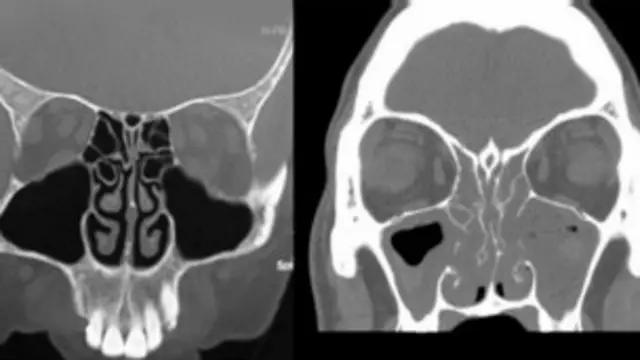

Para ayudar a los pacientes a recuperar el sentido del olfato, Philpott utiliza un sistema de neuronavegación conocido como cirugía bilateral de seno endoscópica asistida por computadora (BiCASS, por sus siglas en inglés).

Para esto, se coloca la imagen de una tomografía computarizada superpuesta a la cara del paciente, lo que deja al descubierto los senos nasales bloqueados, lo que a su vez sirve de guía para permitir una cirugía más completa.

Los estudios han demostrado que esta técnica, más invasiva, puede hacer que sólo el 2% de los pacientes necesiten cirugías adicionales, mientras que de aquellos que se someten a una polipectomía estándar, el 20% requieren cirugía adicional en los siguientes cinco años.